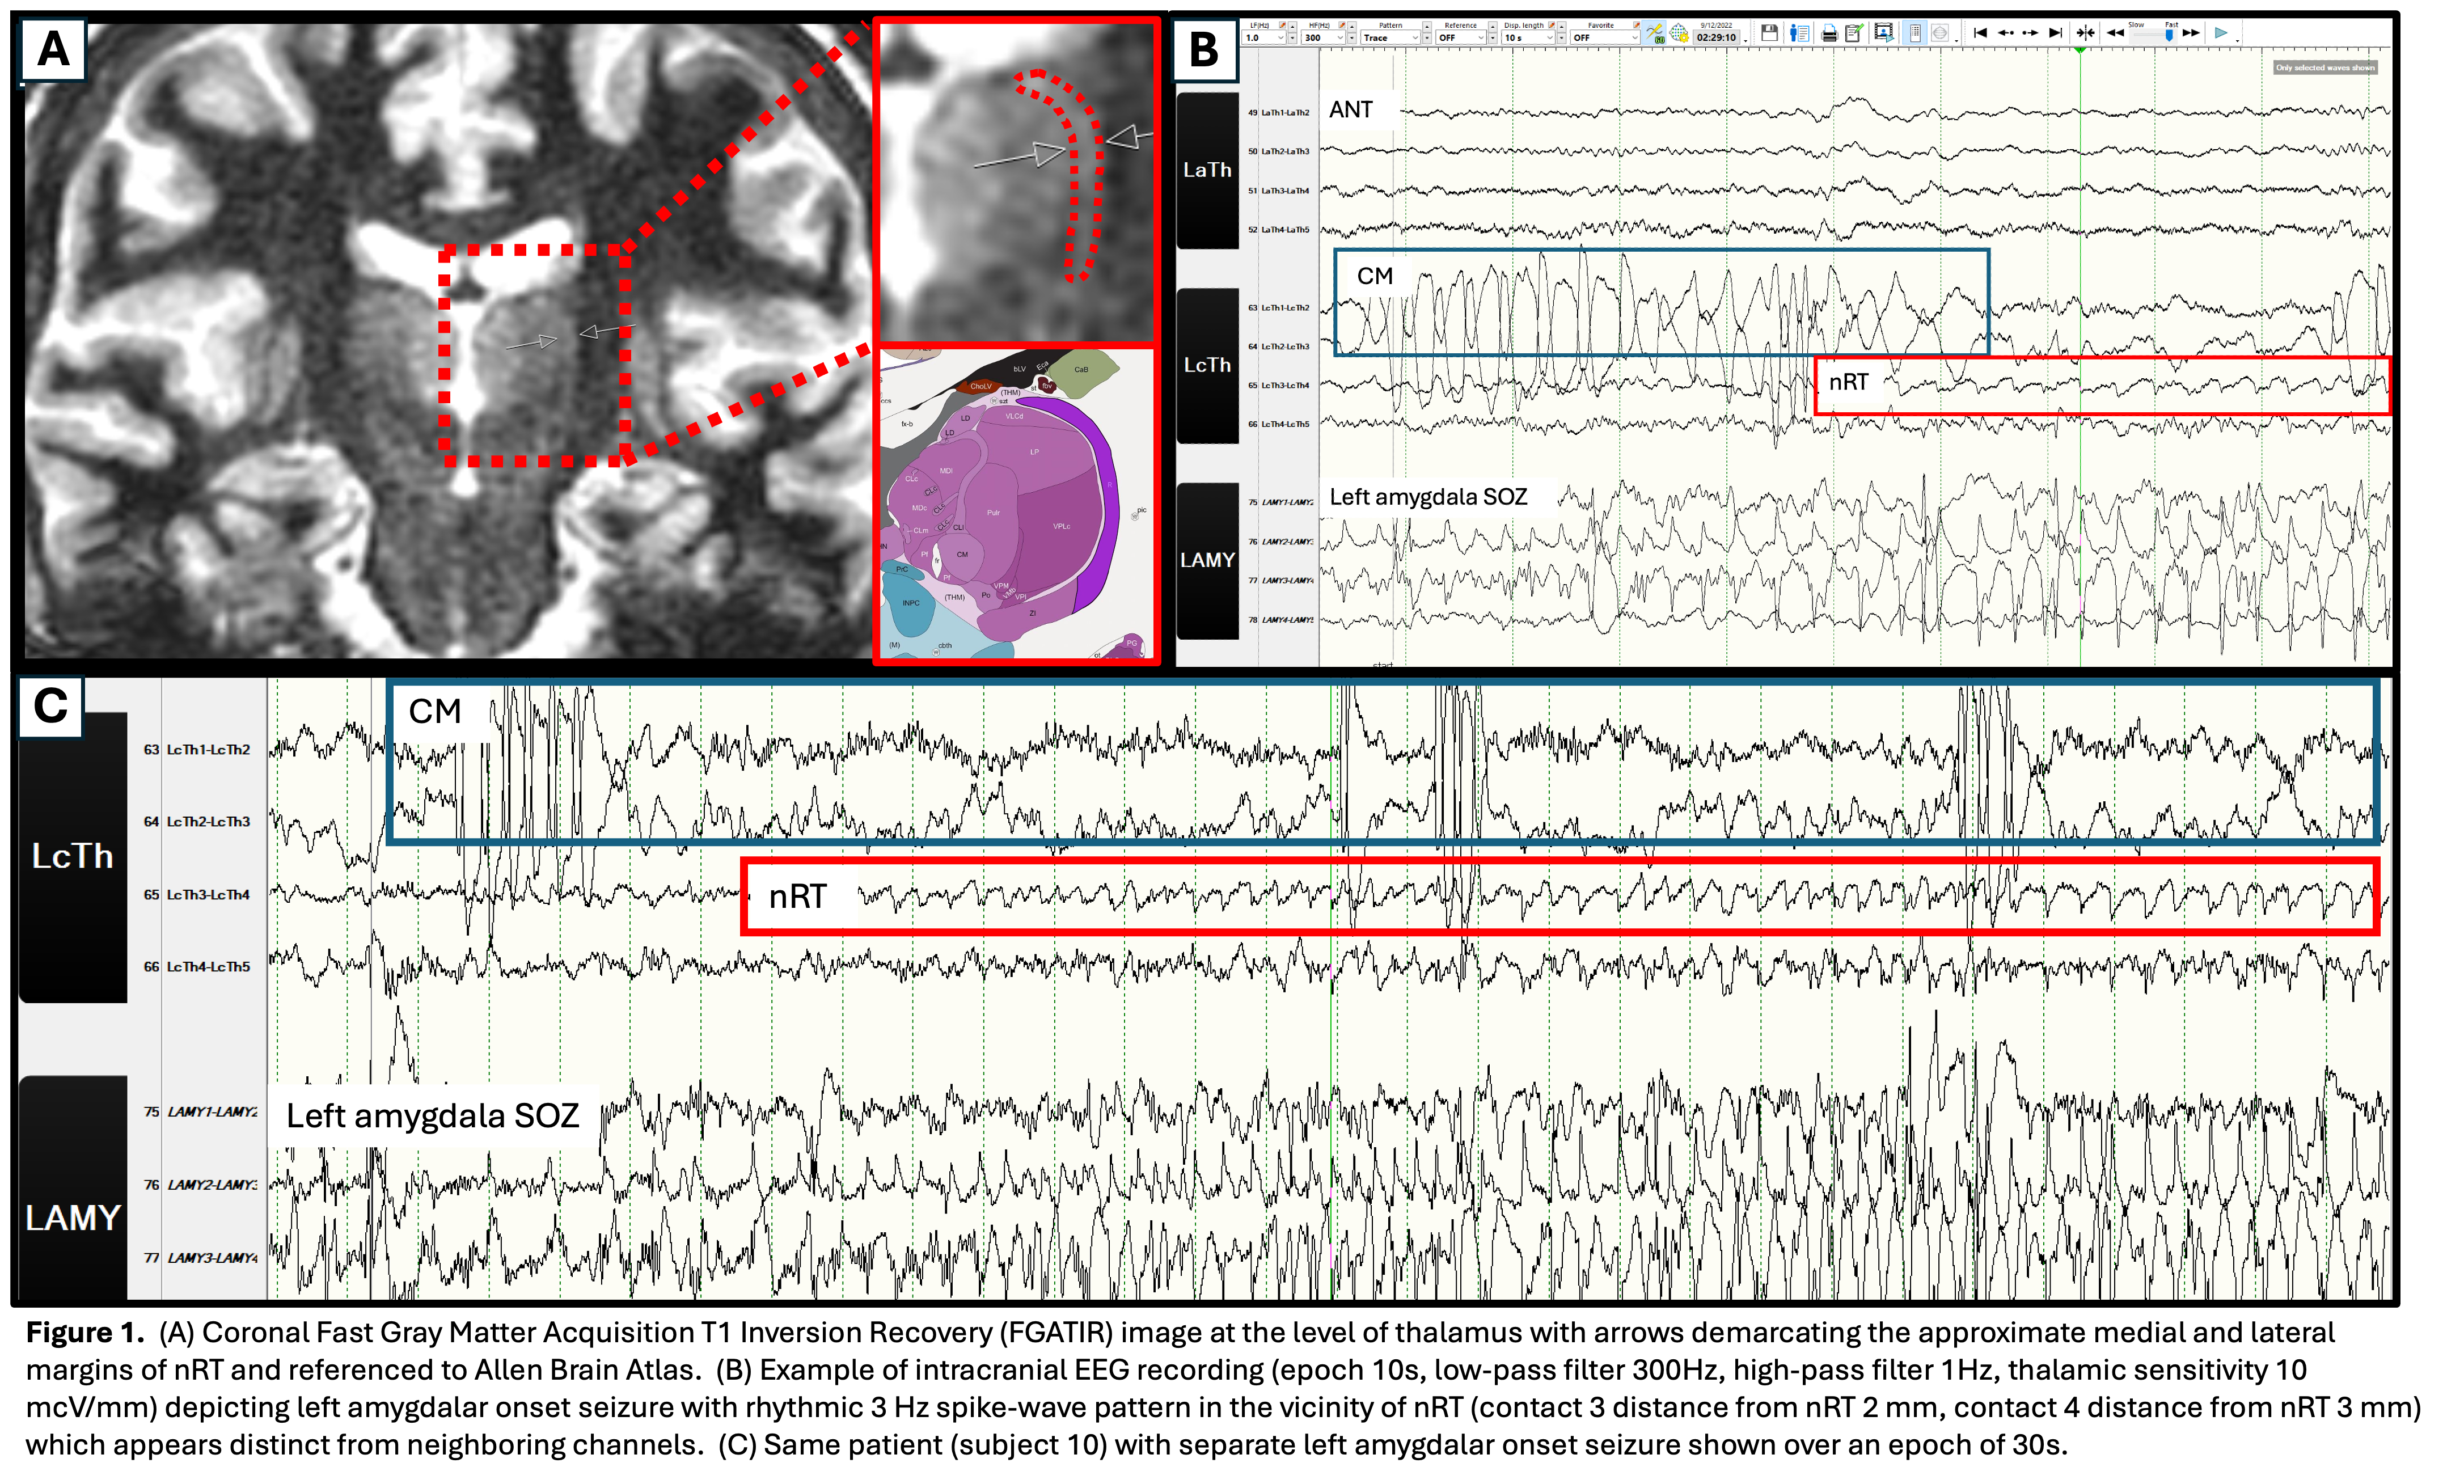

This retrospective study was approved by the Stanford Institutional Review Board (IRB).  An epileptologist reviewed intracranial EEG recordings from 10 medically refractory epilepsy patients who had implanted depth electrodes (5 mm contact spacing) targeting the anterior (ANT) or the centromedian (CM) nucleus of the thalamus, with trajectory traversing near nRT.  Neuroradiologists determined which electrode contact was closest to nRT using thin-cut postoperative brain CT co-registered with 3 Tesla MRI.  Despite having a shell-like structure, nRT was visualized using FGATIR and/or FSPGR sequences and the distance to nearest electrode contact was measured.

Across the 10 subjects (5 female, 5 male) there were 41 focal seizures analyzed.  In 98% of focal seizures, the electrode contact closest to nRT (average distance 1.7 mm, range 0.0 - 4.0 mm) exhibited activity temporally corresponding to discharges at the seizure onset zone.  This activity in the vicinity of nRT occurred earlier than seizure propagation to ANT/CM in 24% of seizures.   In 43% of focal seizures and 50% of patient cases, the ictal nRT activity appeared to be distinct in frequency, morphology, and evolution from the adjacent channels, suggesting involvement beyond volume conduction.  The average time from first ictal EEG pattern at the seizure focus to distinct ictal activity in nRT was 7 seconds (range 0 - 22 seconds).  nRT ictal onset patterns included rhythmical slow spikes, bursts of beta spikes, and rhythmical alpha or theta frequencies.  Distinct nRT activity was seen with seizure onsets localizing to the left hippocampus, left amygdala, left insula, right posterior cingulate, and right superior temporal sulcus.